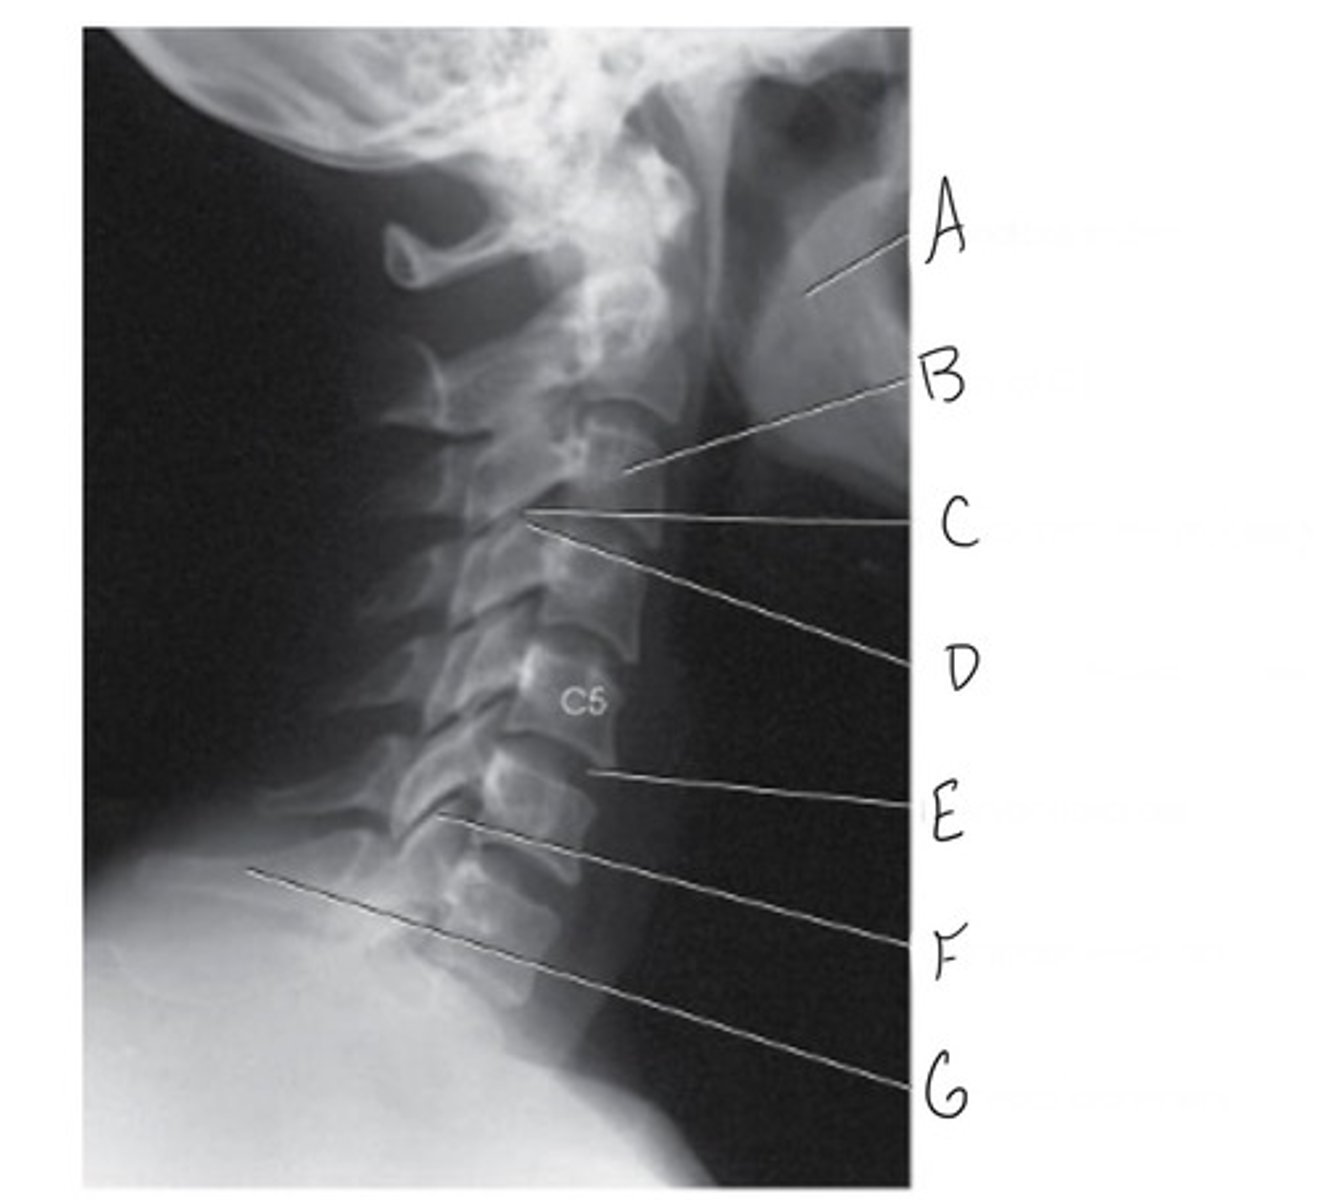

Typical Cervical Vertebrae (C3-C7)

What vertebrae is this?

Body

What is A?

Transverse process

What is B?

Vertebral foramen

What is C?

Lamina

What is D?

Spinous process with bifid tip

What is E?

Superior articular process & facet

What is F?

Pedicle

What is G?

Transverse foramen

What is H?

Articular pillar

What is I?

Inferior articular process

What is J?

Vertebral notch

What is K?

Mandibular rami

Body of C3

Superior articular process

Intervertebral disk

Zygapophyseal joint

Vertebra prominens (C7)

Why is G?